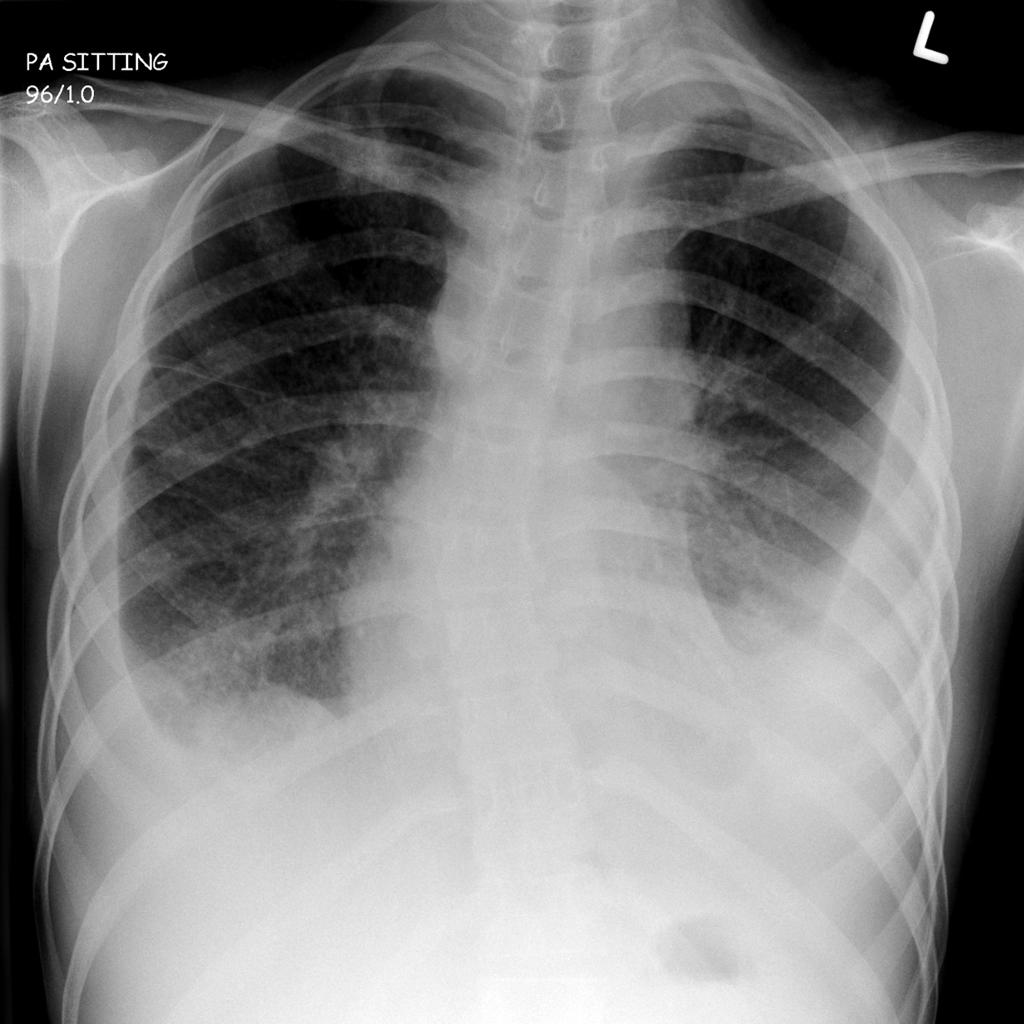

При пневмонии обнаруживаются на рентгене изменения, позволяющие отличить ее от туберкулеза:

- Уплотнение (инфильтрация) участка легких с неявными, размытыми очертаниями или в виде дымки (характерно для снимков при острой форме).

- Усиление легочного рисунка (при интерстициальной форме).

При верхнедолевой левосторонней пневмонии поражается до 5 долей легкого. Заболевания этого органа протекают тяжелее, чем правосторонняя пневмония, при которой поражается 1-3 участка.

Флюорографией при пневмонии чаще выявляется поражение нижних и средних частей с изменениями корня легкого.

- Локализация поражений легочной ткани. При пневмонии инфильтративные тени, характеризующие очаги поражения, просматриваются, как правило, в 3, 4, 5, 7, 8, 9 долях легкого, преимущественно поражая нижние участки. Туберкулез, в свою очередь, имеет одностороннюю локализацию, в большинстве случаев поражая правую долю легких в 1, 2, 6 сегментах.

- Очертания теней. При пневмонии инфильтраты (рентгеновские тени) имеют размытые, нечеткие очертания. В острый период заболевания затемнение напоминает дымку, а по мере развития воспаления интенсивность теней возрастает, но нечеткий характер краев сохраняется. Туберкулез же имеет тени с выраженным четким рисунком.

Затемнение может быть тотальным (покрывать всю легочную ткань) и локальным (занимать небольшой участок). Тотальное затемнение представляет собой тень белого света без четких контуров, занимающую большую часть легких. Она может быть как одно-, так и двусторонней.

Ограниченную тень рентгенологи подразделяют на очаг и инфильтрат. Очаг имеет диаметр до 10 мм, а инфильтрат — более 10 мм. Инфильтрат не имеет четких контуров и чаще всего возникает при пневмонии (воспалении легких), плеврите (воспалении плевры — оболочки, окружающей легкое).